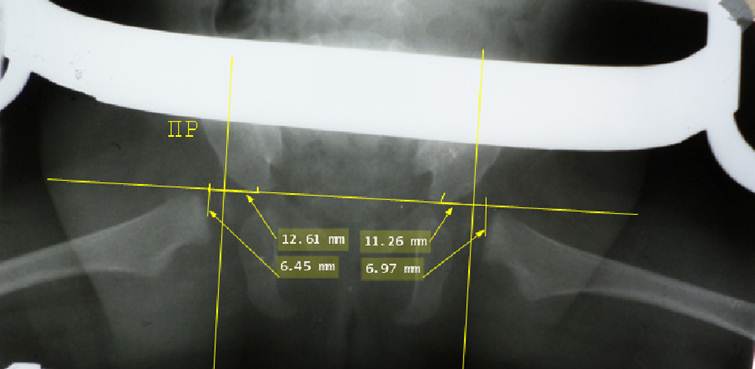

Начинают

расчерчивание с базовой линии Хильгенрейнера: проводят горизонтальную линию,

касающуюся нижних краев теней подвздошной кости. Затем проводят линии,

касательные к крышам вертлужных впадин, или линии крыш вертлужных впадин. Для

каждого сустава отмечают две точки: точка контакта линии Хильгенрейнера с

нижним краем тела подвздошной кости и точка на верхнем крае вертлужной впадины.

Соединяя точки, проводят линию крыши впадины. Угол между линией Хильгенрейнера

и линией крыши впадины называется ацетабулярным углом, у детей 3 месяцев он

должен быть 30° или меньше. Он отражает достаточность глубины впадины: чем он

меньше, тем впадина глубже.

На

верхнем конце рентгеновского изображения бедренной кости четко прослеживается

почти горизонтальная площадка. Это окостеневшая часть нижнего полушария головки

бедренной кости. На площадке надо найти середину и отметить точку, которая

является примерным центром головки бедра. Затем отмеченную точку соединяют перпендикуляром

с линией Хильгенрейнера. Длина отрезка от линии Хильгенрейнера до центра

головки бедра будет вертикальной позицией головки бедренной кости, она должна

быть не менее 10 мм. Расстояние от точки пересечения перпендикуляром линии

Хильгенрейнера до точки её контакта с нижним краем подвздошной кости будет

горизонтальной позицией головки бедренной кости, она должна быть не более 10

мм. При возникновении вывиха головки бедренной кости в вертлужной впадине она

смещается вверх и кнаружи, что проявится увеличением цифры горизонтальной

позиции и уменьшением цифры вертикальной позиции. Схема Хильгенрейнера имеет

недостаток: она привязана к возрасту 3 месяца и учитывает абсолютные цифры

Снимок

нормальных тазобедренных суставов ребенка 3 месяцев, расчерчивание по схеме

Хильгенрейнера. Ацетабулярные углы с обеих сторон равны 28°, вертикальная и латеральные позиции головки бедра с

каждой стороны равны. Присмотревшись, вы можете заметить формирующиеся ядра

окостенения головок бедра с обеих сторон.